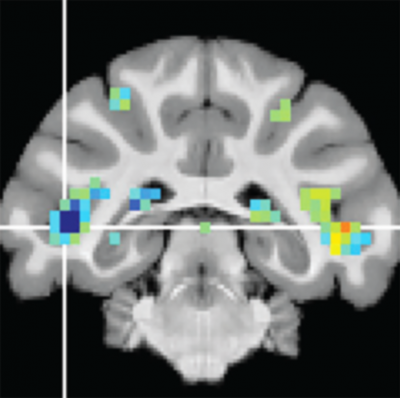

Slice of brain scan showing highlights in the cortex

fMRI scans reveal activity changes in the fSTS. Image courtesy of Richard Krauzlis, Ph.D.

Krauzlis and his colleagues described the discovery of the fSTS in a study published last year with David Leopold, Ph.D., chief of the Section on Cognitive Neurophysiology and Imaging at the National Institute of Mental Health (NIMH). Together they had the monkeys complete the visual attention tasks inside a functional magnetic resonance imaging (fMRI) machine. fMRI imaging revealed that a specific region in the temporal cortex—later named fSTS—was, like the superior colliculus, strongly activated during these attention tasks. This was surprising because this cortical region was not yet known to be important for visual attention.